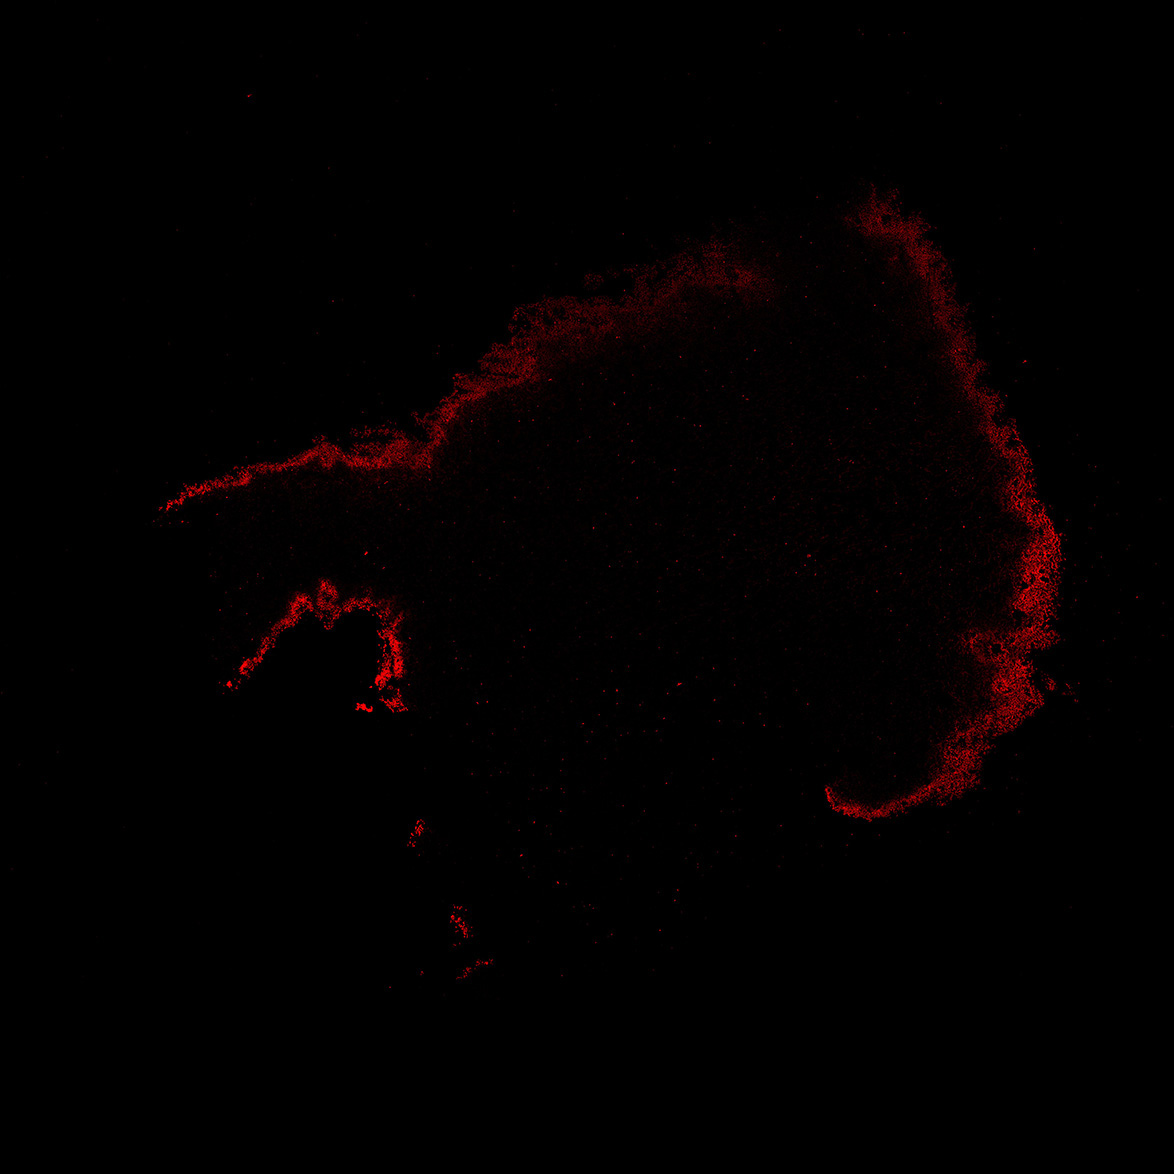

TH

7PCW human midbrain

11PCW human midbrain

13PCW human midbrain

15PCW human midbrain

17PCW human midbrain

19PCW human midbrain

22PCW human midbrain